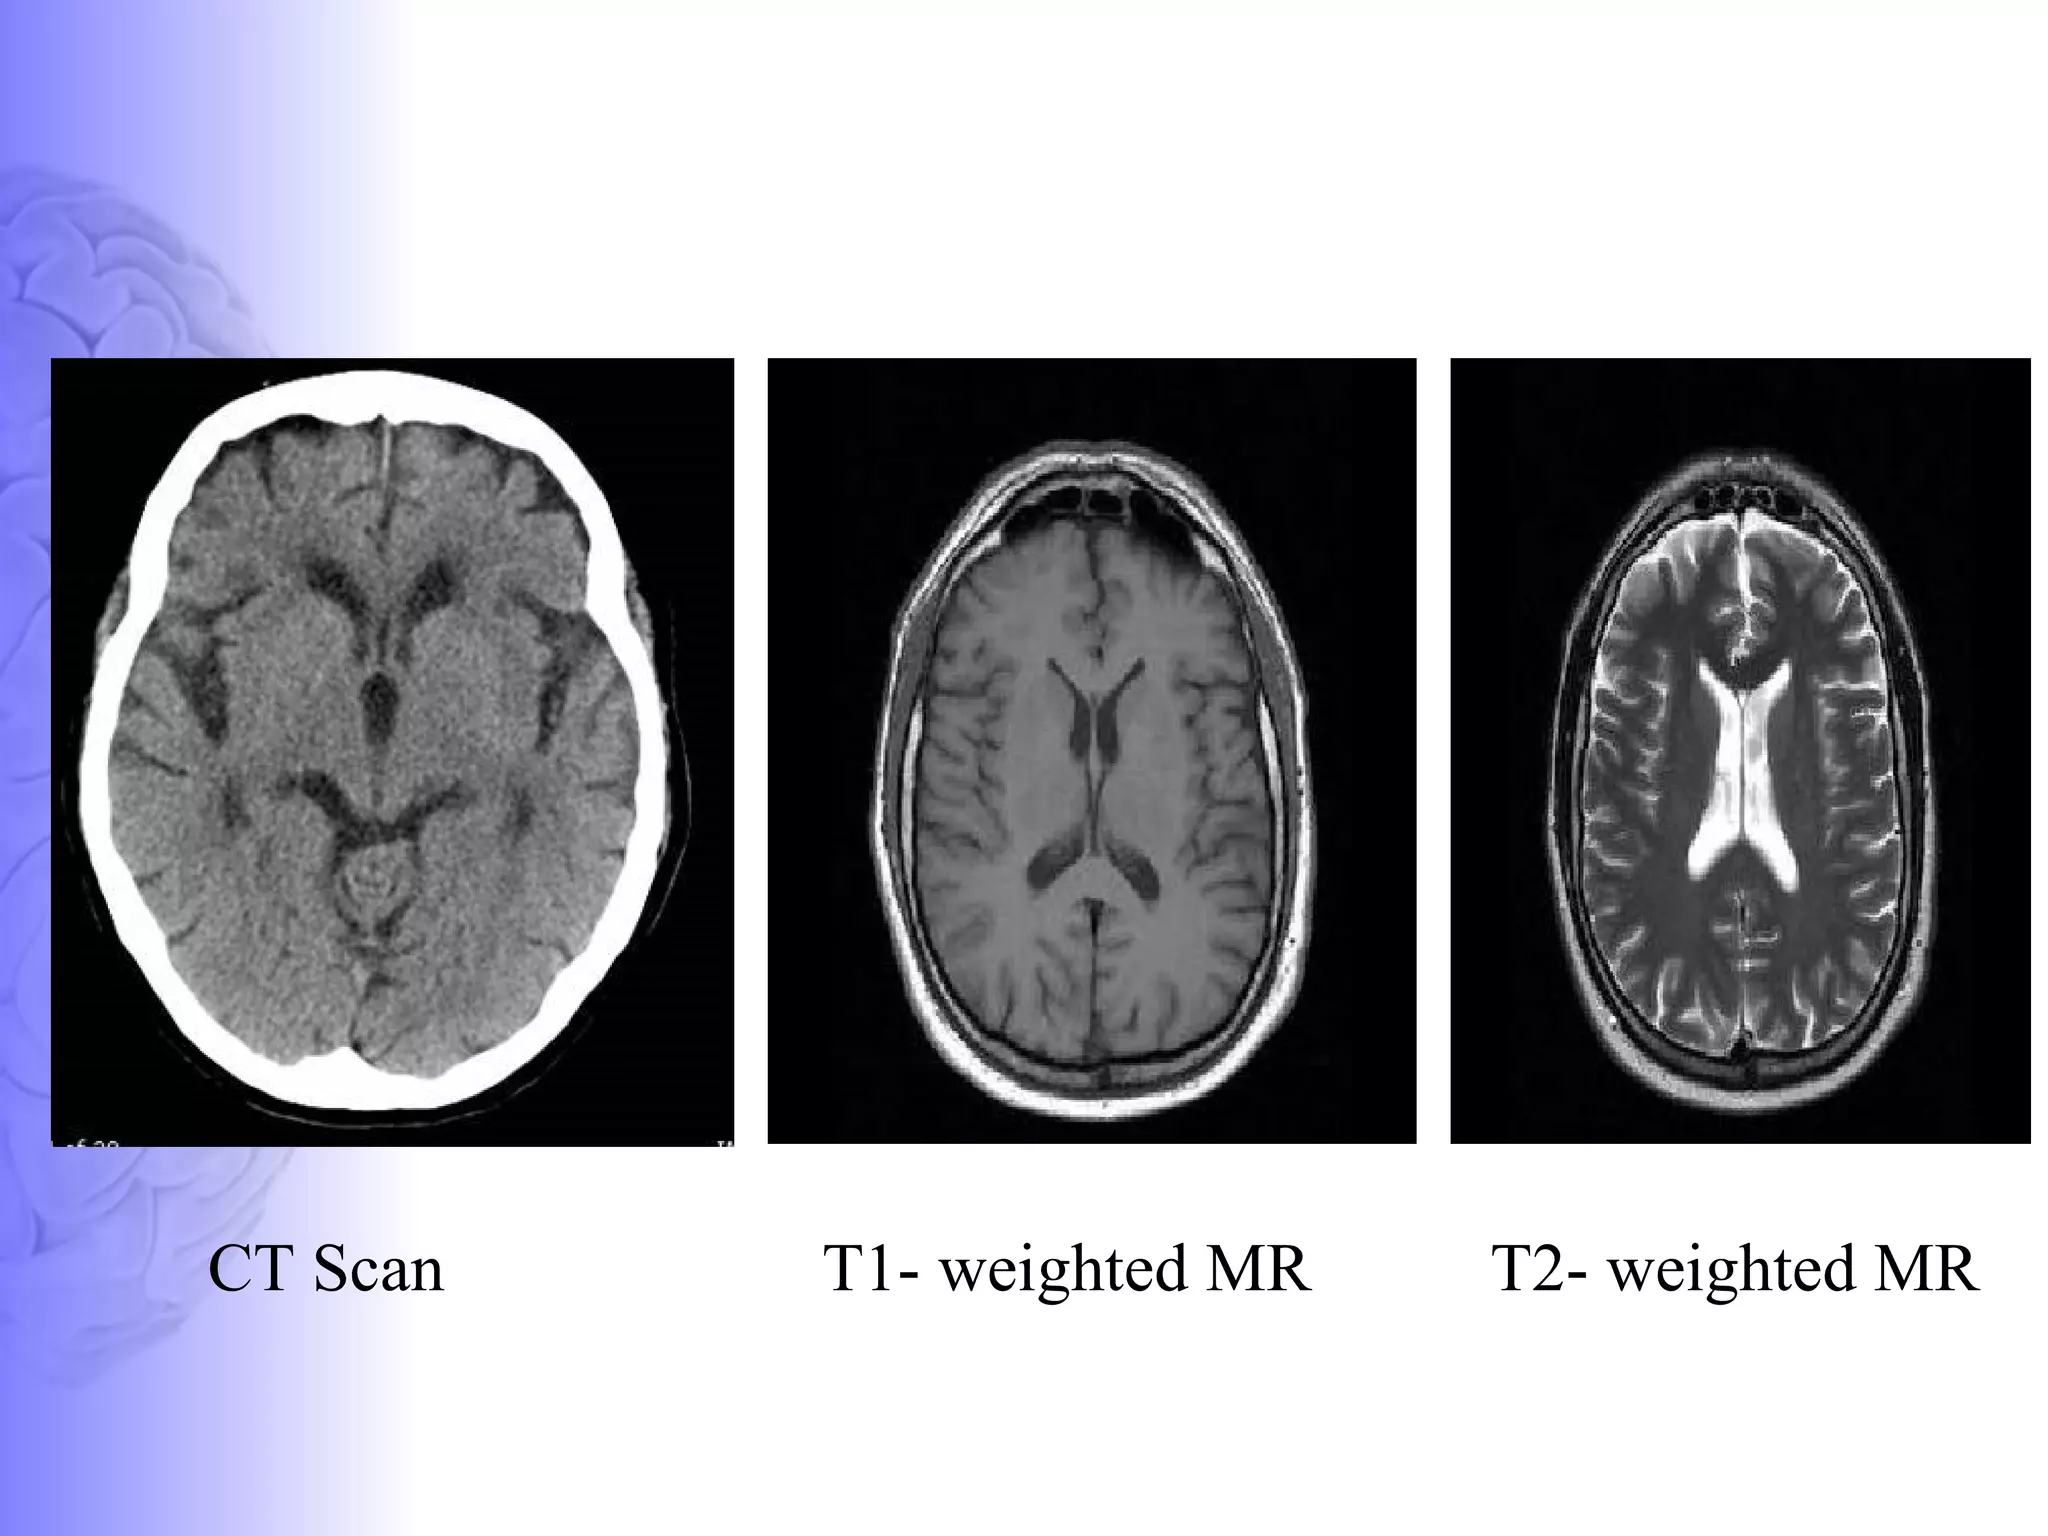

Basics - MRI T1 weighted imaging- Basis is the longitudinal relaxation (spin lattice relaxation) T1  image created typically by using short TE and TR times (TE –echo time ::TR – repetition time ) Fat (larger longitudinal and transverse magnetization) - Bright on a T1  Water (less longitudinal magnetization)-Dark on T1

Basics - MRI T2 weighted imaging- Basis is the transverse relaxation (spin spin relaxation) T2 created typically by using longer TE and TR times. Fat (larger longitudinal) - Dark on a T2  Water (less longitudinal magnetization)-White on T2

T1- weighted MR  T2- weighted MR  CT Scan